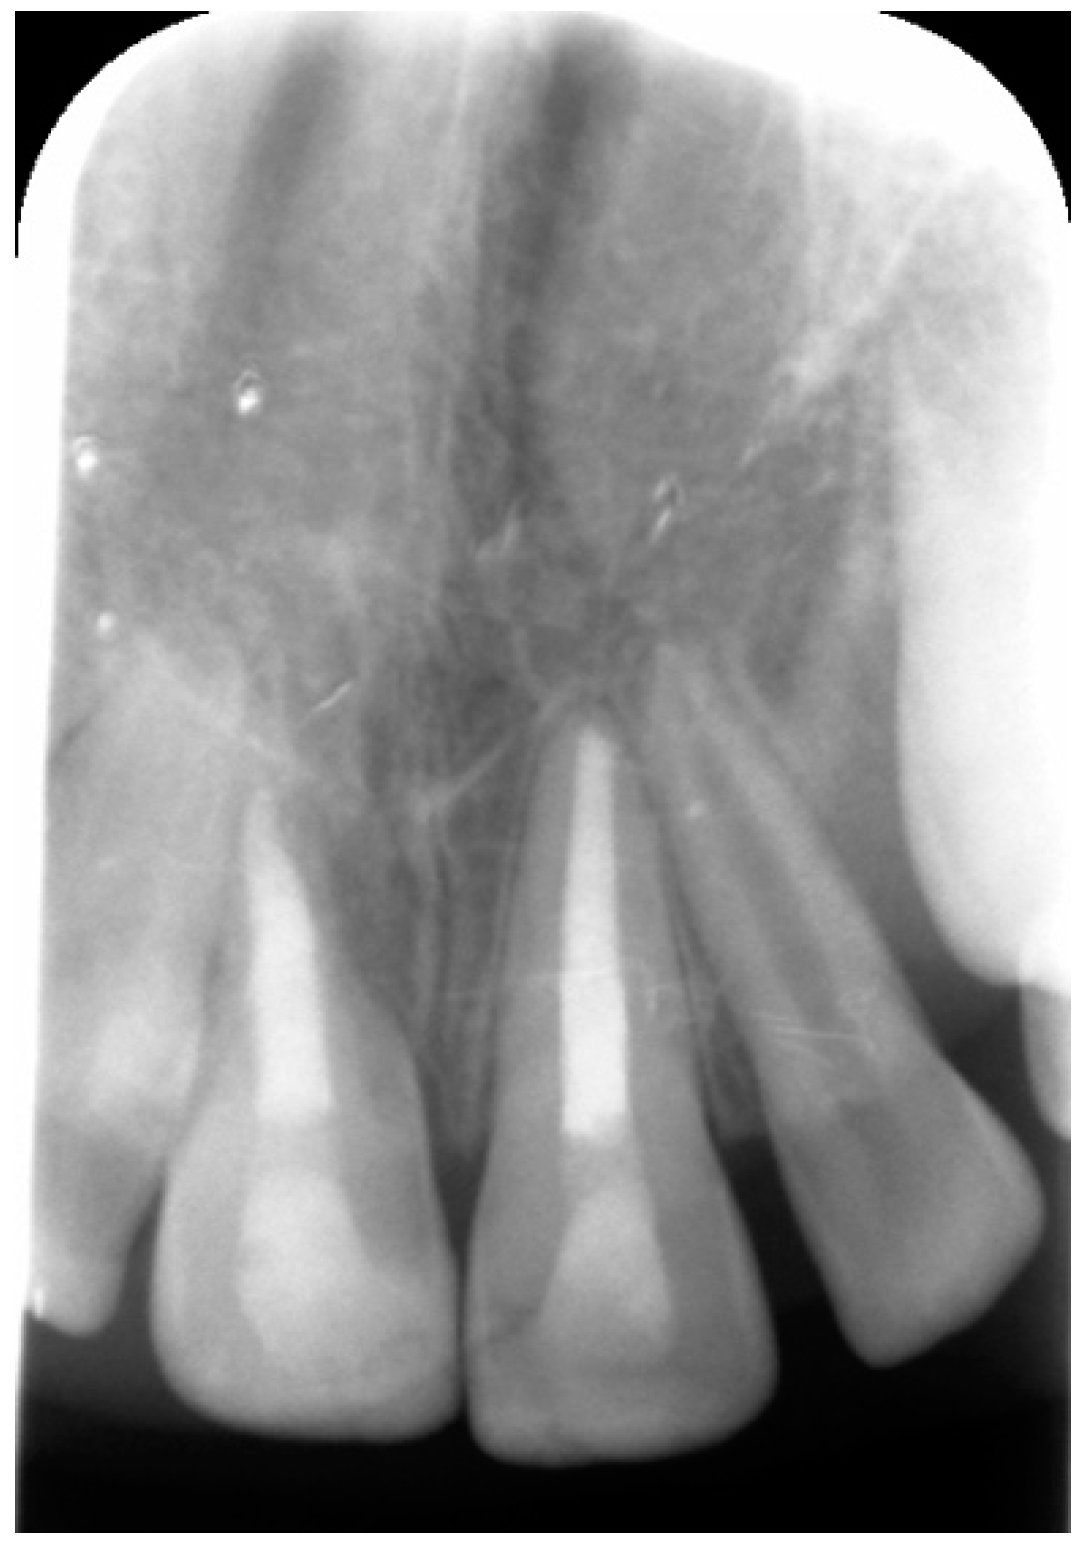

2. Case Report